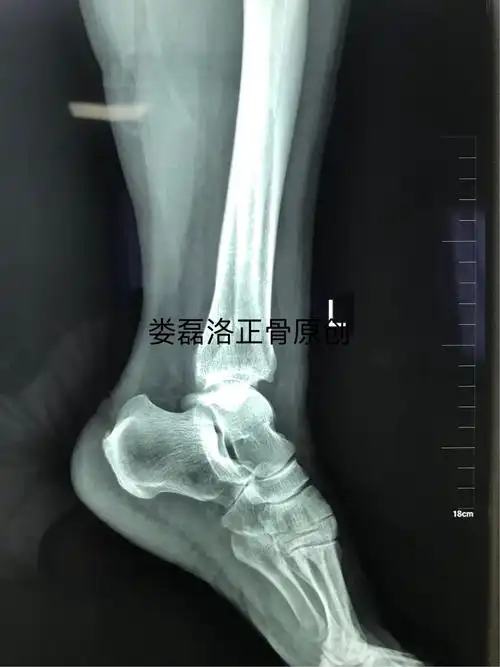

涉及内测三角韧带损伤的一例踝关节骨折